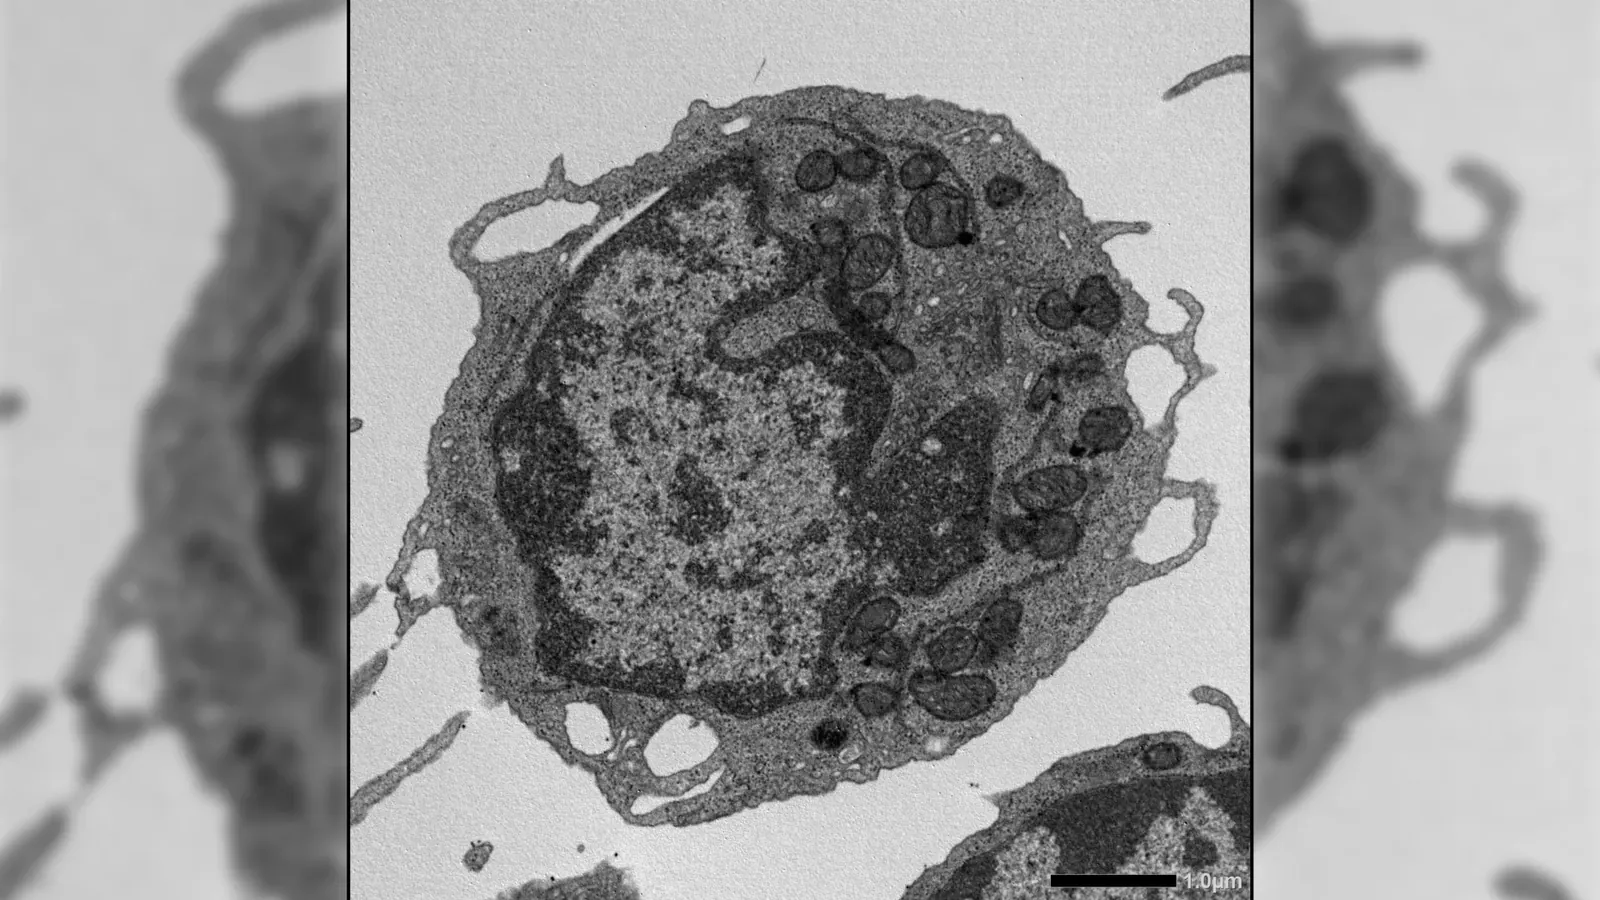

Biotechs race to turn aging science into cell-based therapies

From encapsulated cell therapies to gene-driven breakthroughs, a new wave of biotech is targeting the biology of aging. Heart disease, diabetes, Alzheimer’s – each treated as its own battle. Aging, meanwhile, sat in the background, accepted but not addressed, but that perspective is starting to feel outdated. A new wav...

Why it matters This preclinical signal clarifies which mechanisms justify expensive validation steps before advancing into human-focused longevity programs.